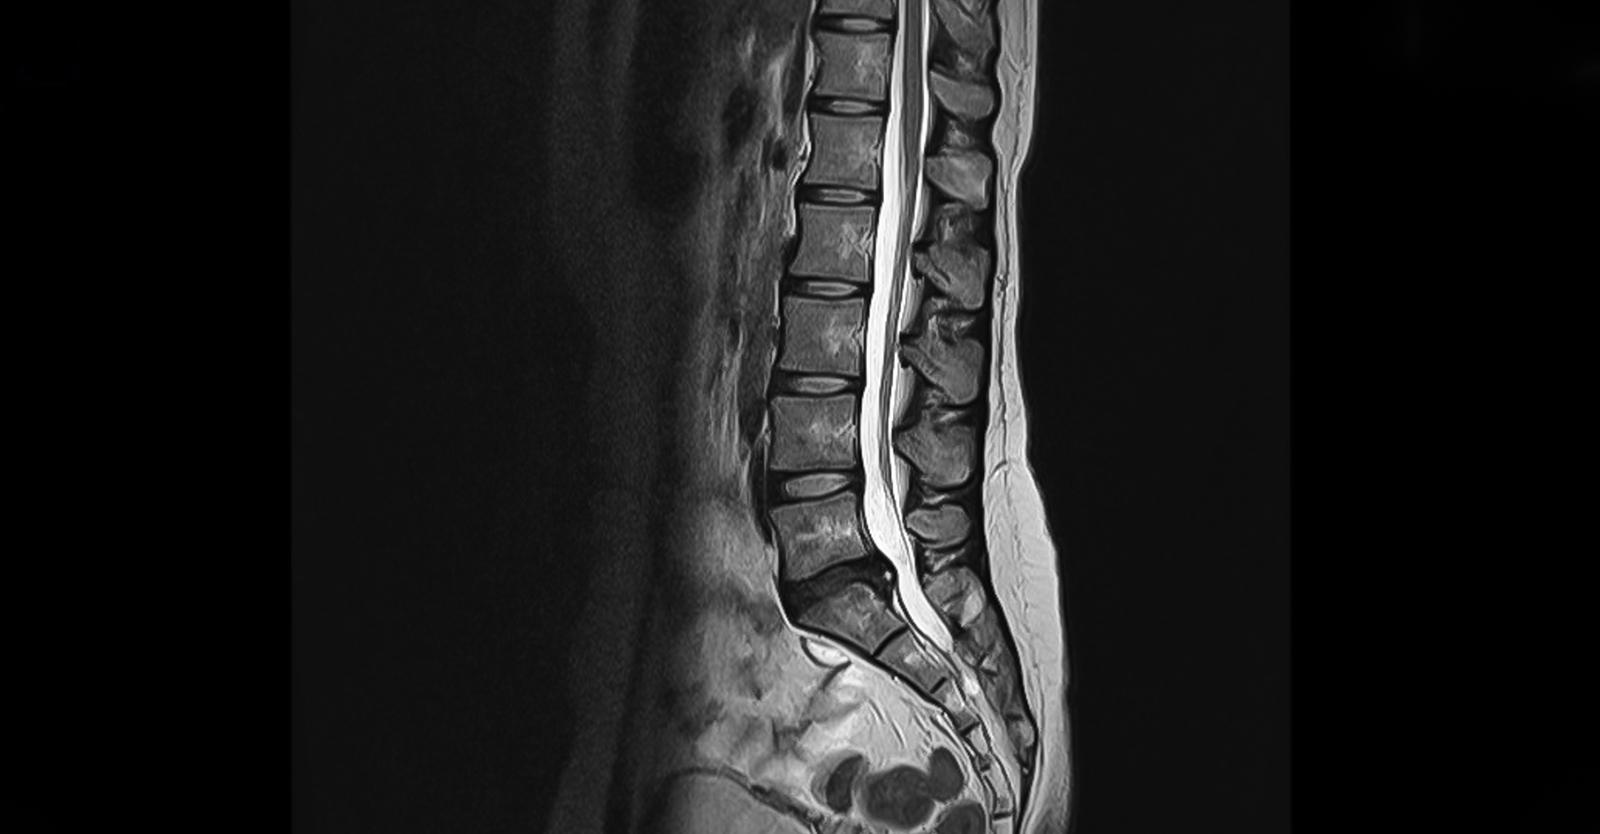

此外,內地的MRI報告,通常都只有簡體字版本,對於一直以英語受訓、不熟悉簡體字的醫生來說,或需要以翻譯軟件來協助理解報告內容。再者,撰寫報告的,既是內地放射科醫生專家,萬一在影像診斷上有任何錯漏,以致本地醫生基於報告而造成治療上失誤,法律責任屬誰卻是一大問號。更重要的是,當計劃較為複雜的手術時,例如需要在脊椎內植入金屬假體,醫生通常需要更多影像數據作術前評估,然而內地的MRI報告,卻通常沒有附上光碟或USB來讓醫生作詳細檢閱。故此,醫生或會建議病人在接受大型手術前,在本地再照一次MRI來覆檢,而病人在平衡利弊和風險下,都會欣然接受。